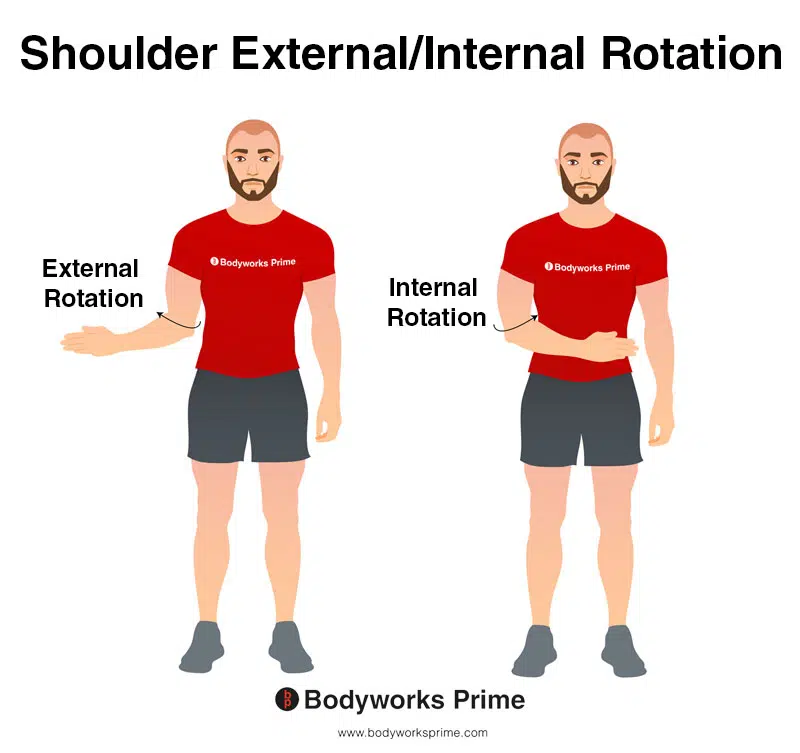

muscles involved in shoulder external rotation

deltoid posterior

infraspinatus

teres minor

supraspinatus

muscles involved in internal rotation

deltoid anterior

pectoralis major (sternal and clavicular )

teres major

latissimus dorsi

subscapularis

biceps brachii (short head)